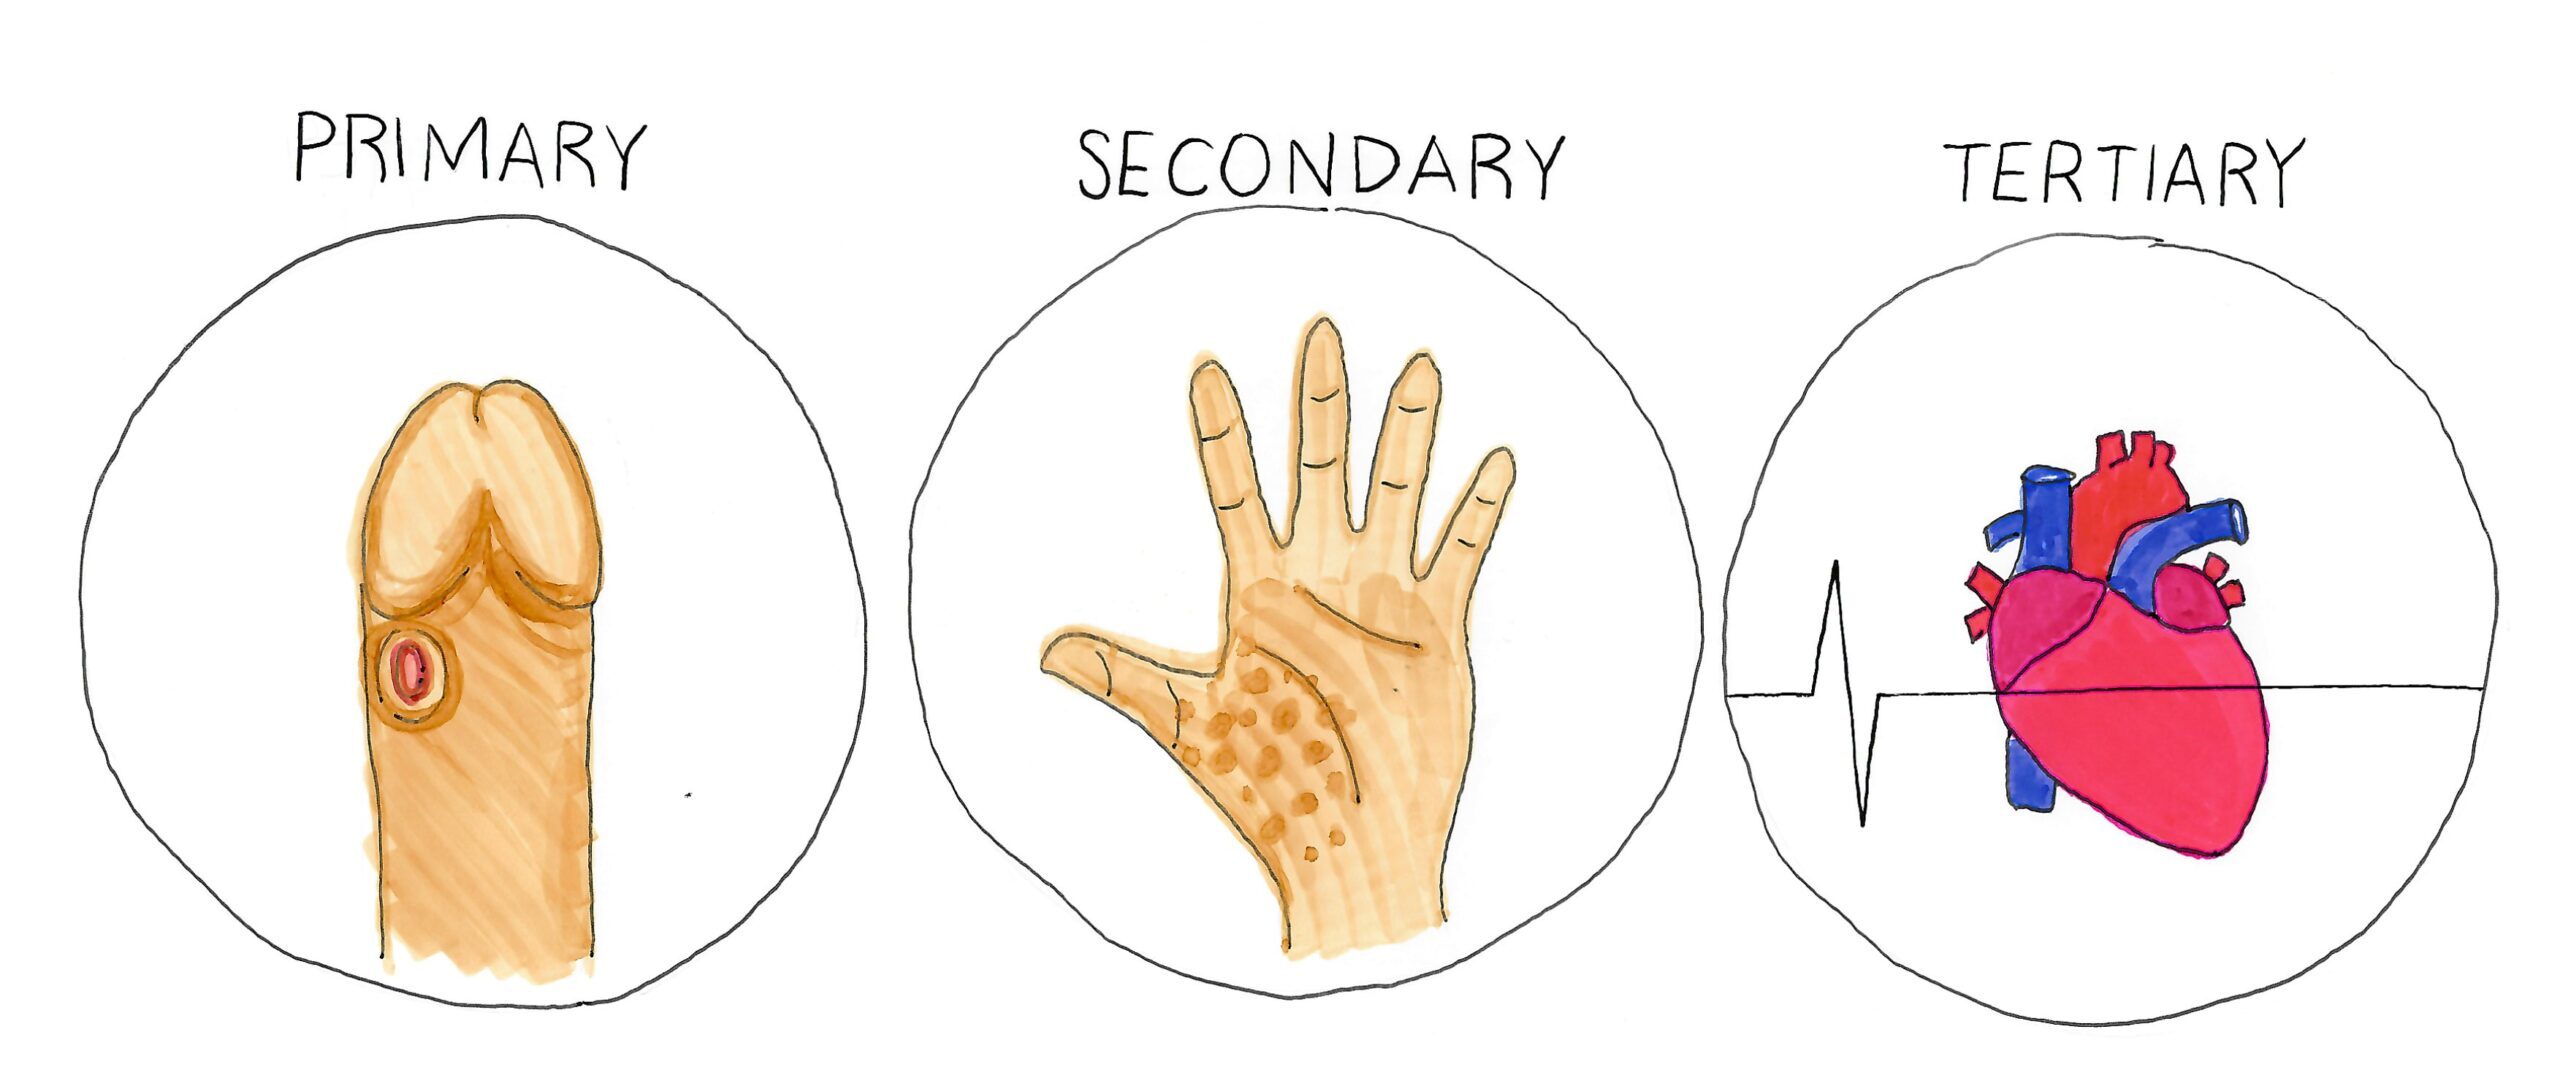

Signs and Symptoms

Each stage of Syphilis has different symptoms, or none.

Primary Syphilis

Also known as ‘Stage One Syphilis’ has any one, or a multiple, of these symptoms, OR NONE.

- Very small pimple or tear in skin, with no tenderness or pain.

- Painless spot on your tonsil.

- A feeling like you have bitten your cheek.

- A small tear in the skin (can be very small).

- A sore with raised edges, small or up to two centimetres wide.

- Spots on body that appear like a small sweat rash, not itchy.

- A shiny, glossy or mucousy patch on the skin that may resemble an ulcer.

- Something that looks like a wart, but goes away.

- Something that looks like a herpes sore, but goes away and could be painless.

Primary Syphilis lasts for a few weeks, and symptoms can be painless or tender. For this reason, many people do not notice the symptoms. The symptoms go away after a few weeks. At this point, Secondary Syphilis develops.

Primary Syphilis can overlap with Secondary Syphilis for a few weeks.

Secondary Syphilis

Also known as ‘Stage Two Syphilis’ has any one, or a multiple, of these symptoms, OR NONE.

Body rash, comes and goes

- Reddish or brownish or blotchy.

- Not itchy and not infectious.

- Can be on soles of feet and hands, or anywhere.

- The rash comes and goes, and can be small and not noticeable.

General feeling of being unwell, comes and goes

- Flu-like symptoms, but not infectious like a normal flu.

- Sore throat.

- Fatigue, generally feeling low energy .

- Swollen lymph nodes.

- Hair loss more than usual (not always noticeable).

- Symptoms come and go, appear to resolve on their own.

Tertiary Syphilis

Note: Some people have no symptoms.

- Problems controlling muscle movements.

- Numbness.

- Vision problems (starting to go blind).

- Hearing problems (starting to go deaf).

- Dementia symptoms.

- Seizures, hallucinations, stroke, mental disturbance.

- Incontinence.

- Meningitis.

- Non-cancerous lesions on the skin, mouth and internal tissues.

- Inflammation of the aorta in the heart, this can cause aortic aneurysm.

- Aortic aneurysm—thinning of the lining of the aorta in the heart. If this bursts the person will likely die.